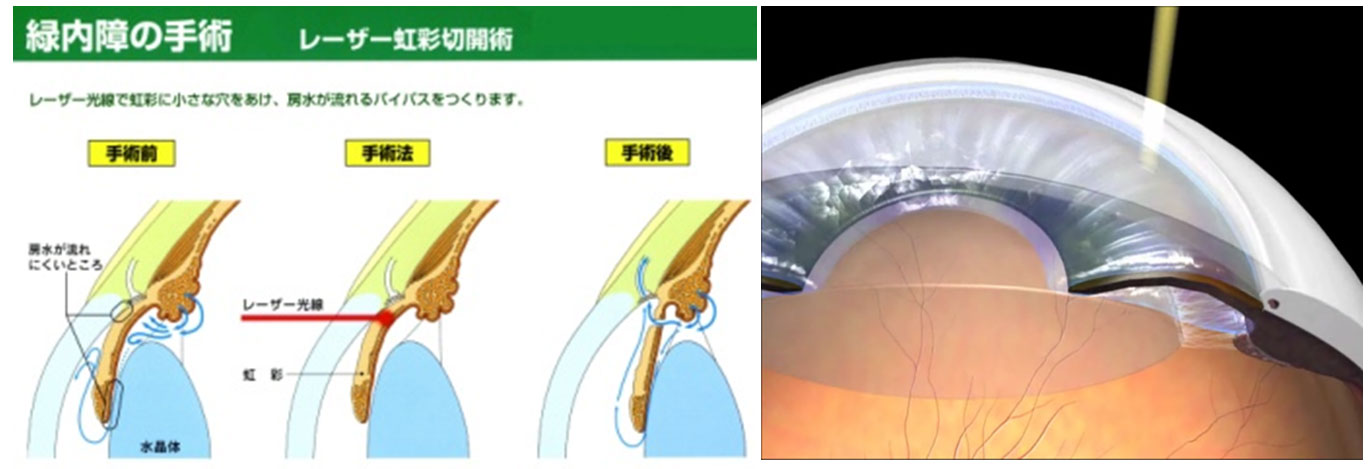

レーザー虹彩切開術

レーザー線維柱帯形成術